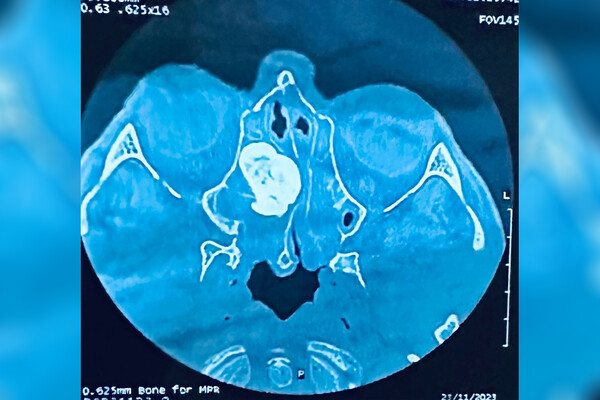

56-летний мужчина обратился в больницу с жалобами на затрудненное дыхание, постоянный насморк и сильные головные боли. В ходе обследования в носовых пазухах пациента была обнаружена доброкачественная опухоль большого размера.

Остеома блокировала соустья с пазухами носа, препятствуя оттоку слизи и аэрации пазух. Было принято решение о проведении малоинвазивной операции, без единого разреза медики удалили новообразование. Спустя несколько дней пациента выписали на амбулаторное лечение.